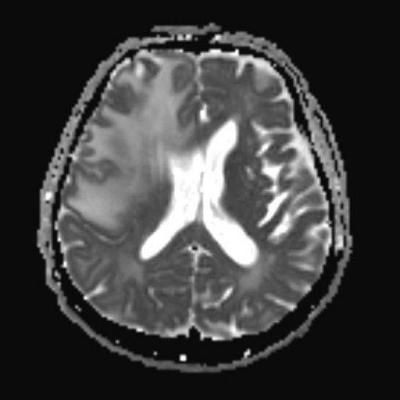

- A) Aksiyel planda FLAIR sekansta asimetrik kortiko-subkortikal vazojenik ödemi düşündüren yüksek sinyalli hafif ekspansil lezyonlar (turuncu ok).